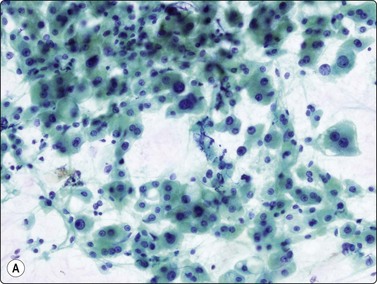

Liver cell adenoma (Fig. 10.13)

image

Fig. 10.13 Liver cell adenoma

Poorly cohesive epithelial cells resembling hepatocytes, bland nuclei, Kupffer cells but no bile duct epithelium (A, H&E, IP; B, Pap, HP); (C) Corresponding tissue section (H&E, IP).

Criteria for diagnosis46

Moderate to markedly cellular smears arranged in clusters or tissue fragments,

Monotonous cells resembling normal hepatocytes with pale or vacuolated cytoplasm,

Absence of bile duct epithelium.

Problems and differential diagnoses

Adenoma is difficult to differentiate from other low grade hepatocellular lesions, ie FNH and well differentiated hepatocellular carcinoma.

The differences in cytological patterns between adenoma and well-differentiated carcinoma can be subtle and will be discussed in the section on hepatocellular carcinoma. The cytoplasm is more abundant, less fragile and better defined with more distinct cell borders in adenoma, the nuclear : cytoplasmic ratio is consistently low, and single, bare neoplastic nuclei are less apparent (Fig. 10.13). Marked anisokaryosis is not a feature. Adenoma and FNH both comprise benign hepatocytes. In the absence of abundant bile duct epithelium, which favors FNH, distinction between them is not possible.41,106